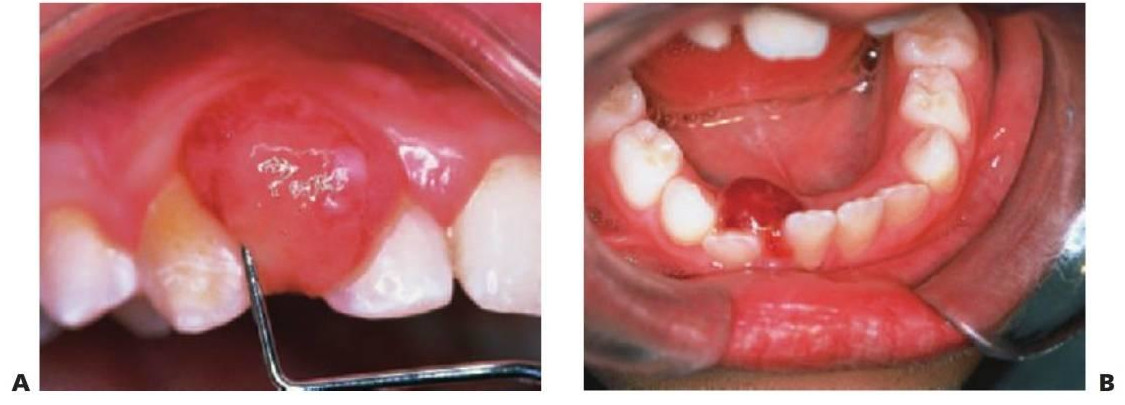

Se trata de uno de los epúlides más frecuentes en niños y resulta de una reacción fibroepitelial a la placa. Suele aparecer en las papilas interdentales y su color varía desde el rosa al rojo y el amarillo; los amarillos están ulcerados. El nombre de granuloma piogénico es utilizado por algunos para describir las lesiones en extremo vascularizadas (fig. 8.15A).

Épulis de células gigantes/granuloma periférico de células gigantes

Estas lesiones suelen presentarse en la región de la dentición temporal y suelen tener un color púrpura oscuro. En ocasiones se observa una pérdida de hueso en la cresta alveolar que da lugar a una «copa radiográfica». Es importante asegurarse de forma radiográfica de que no existe un componente intraóseo, puesto que en ese caso el diagnóstico sería el de granuloma central de células gigantes. Como sucede con las lesiones de células gigantes del maxilar y la mandíbula, se debe incluir el hiperparatiroidismo cuando se lleve a cabo el diagnóstico diferencial (fig. 8.15B).

Se denomina así al crecimiento folicular justo antes de la erupción de los dientes. Estas lesiones tienden a presentar un color negro azulado, ya que pueden contener sangre, y no precisan tratamiento salvo en caso de infección. Se debe tranquilizar al niño y a los padres y dejar que el folículo estalle de forma espontánea, o bien, se puede abrir de forma quirúrgica si se infecta (fig. 8.13).